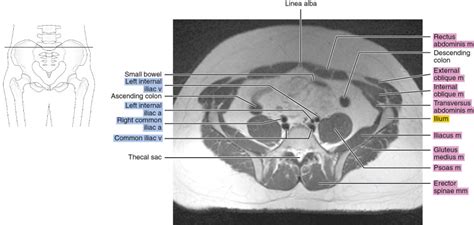

Normal And Variant Pelvic Anatomy On MRI | Radiology Key

Normal and Variant Pelvic Anatomy on MRI | Radiology Key radiologykey.com